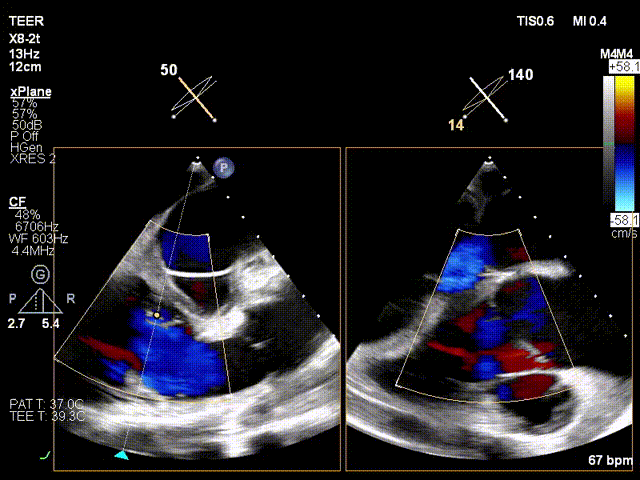

Ultrasound Evaluation:

- Type valve with type IIIb quadricuspid malformation and severe insufficiency (mean vena contracta: 7.4mm).

- Regurgitation orifices located at the anteroseptal and posteroseptal commissures, with a 5.7×3.3mm gap detected in the center.

Preoperative critical regurgitation (5+)